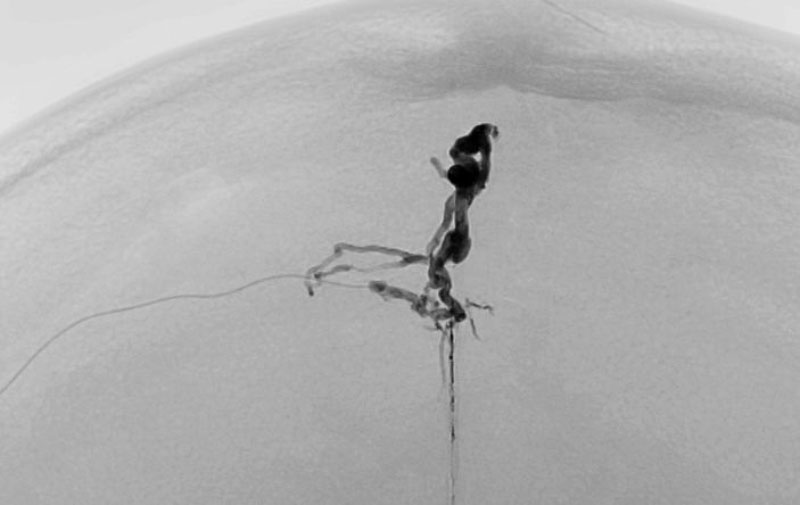

1615

'26年2月21日

硬膜動静脈瘻

50代

大阪府の病院

手術写真

治療

前